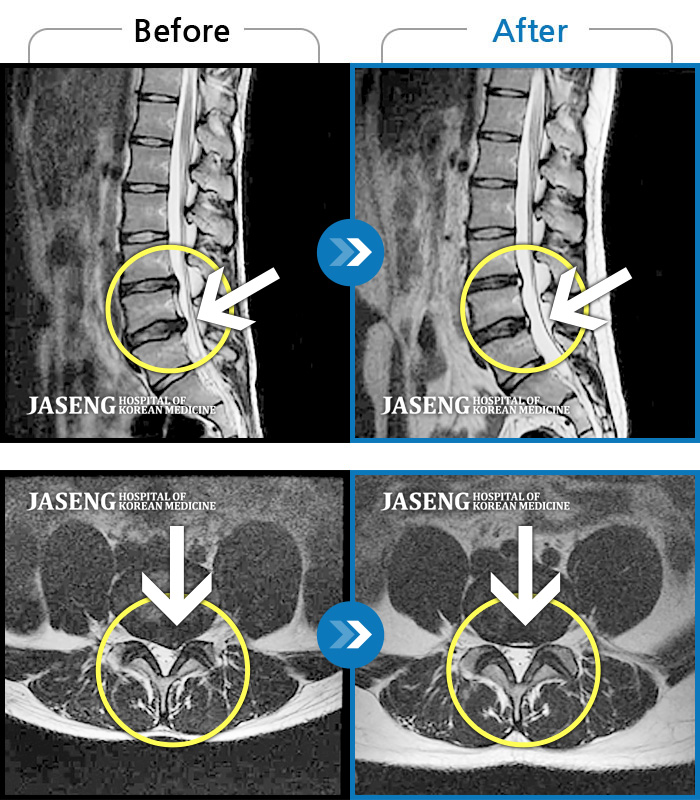

휴직중 허리디스크로 걷지도 못하고 정형외과에서 전부 수술을 권유하는 저에게 비수술로 희망을 주셨어요~^^

지금도 통증이 있으면 통원을 가는데 갈때마다 한결 같으신 원장님 추천합니다~^^